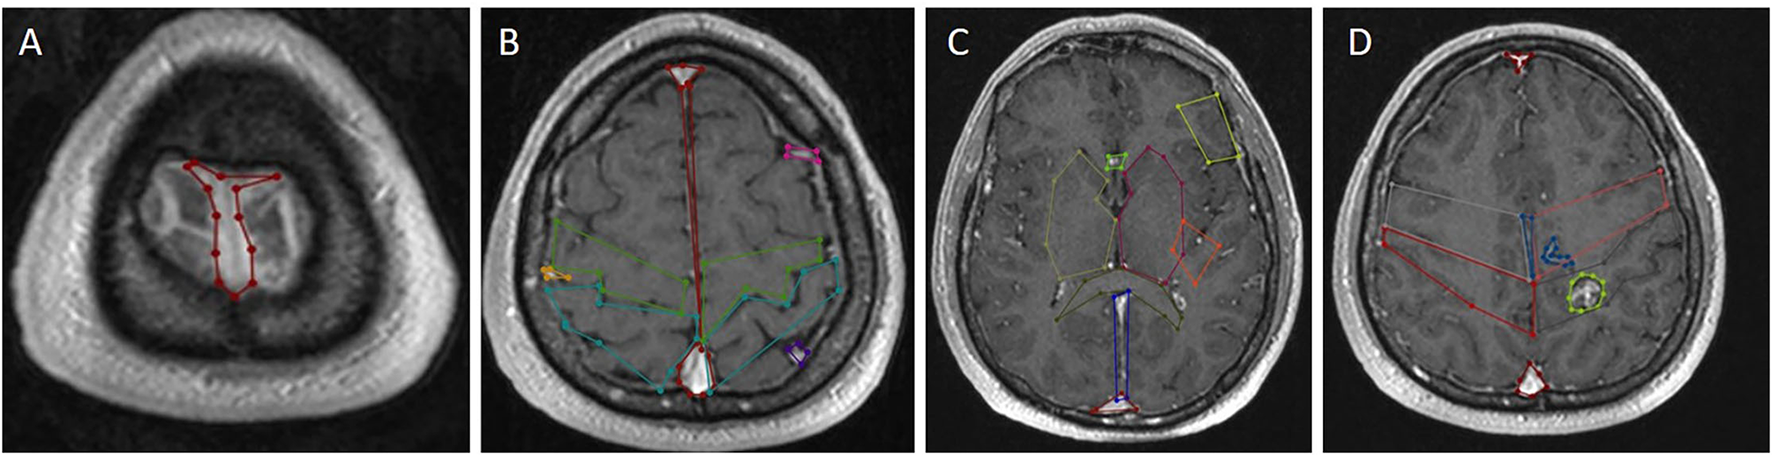

The agent interacts with the environment (is extracted in Algorithm 6 in Supplementary Material) in two ways exploiting (selecting action with the highest value by referencing the Q-table) and exploring (random action selection). Before starting the Q-learning algorithm, all the points (coordinates) on the paths are classified by using the corresponding labeled structures. Thus, the points of all structures belonging to the same class (label value) in different layers are gathered under an array. All the points are considered as a node, and then the reward and penalty scores are assigned to nodes in each class by considering the penalty score of the critical structures, and “1” penalty score is assigned to all other nodes where the agent can interact in. Each node has a neighboring node. If a node is not on the edge or corner, it has eight neighboring nodes (right, left, up, down, bottom-right, bottom-left, top-right, and top-left) over the same layer. The same node has 18 different neighboring nodes over the one upper layer (9 neighboring nodes) and one lower layer (9 neighboring nodes) (Figure 5). The penalty scores of all these 27 different nodes are assigned by considering the penalty score of each class. Then Q-learning algorithm is executed over these nodes to find the best possible nonlinear surgical access paths (Algorithm 7 in Supplementary Material).

We used (512 × 512 × 144) axial T1-weighted MRI images of one patient with a brain tumor in DICOM format as a case study. We utilized 16 × 16, 32 × 32, 40 × 40, and 64 × 64 path dimensions to evaluate the success of the proposed system architecture. In the first stage, 20 optimal linear paths were extracted for each dimension by using the new heuristic-based algorithm. The optimal nonlinear path was extracted by using the starting points found in the 16 × 16 path dimension. For the 16 × 16 path dimension, the proposed heuristic found 745,984 possible entry points. The areas in Table 2 and the target tumor tissue were accepted as reference points. This algorithm gave input fields of desired diameter and size. These 745,984 linear paths were compared according to the reward and penalty points. By using the intermediate steps, the 20-optimal linear paths were chosen. Then the starting points of these paths were used as reference entry points of the Q-learning algorithm (Figure 4) in the second stage. Then, a matrix size of 78,030 × 78,030 was created and worked on 50 × 25 × 78,030 points for Q-learning. Extracranial areas were excluded. It was enough to find 500,000 epoch paths in a 16 × 16 × 35 environment, and it almost took 70 min. The Q-learning algorithm returns as the best way “node” (Figure 5). Then, the positions of these node values in the matrix were found and the x, y, and z coordinate values were reached. Thus, the coordinates representing the best path were extracted from the DICOM images. The most ideal transcortical tumoral pathway was revealed in Figure 6.

Figure 5. The most ideal cortico-tumoral approach is recommended by RL. Images were added one after another to show the nonlinear pathway. RL extracted the most optimal pathway by performing a random-onset point analysis of the entire intracranial area. Demonstration of the approach reaching the tumor from the base of the postcentral sulcus. (A) howing the pathway in coronal sections. (B) Showing the pathway in sagittal sections. (C) Showing the 3-dimensional pathway with image processing.

Figure 6. The figure illustrates the proposed system architecture for finding linear and nonlinear access paths for brain surgery.